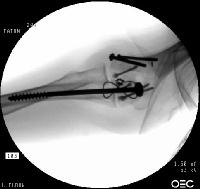

Open reduction via olecranon osteotomy.  The ulnar nerve is  retracted with a penrose drain. The articular surface was reconstructed, then secured to the shaft. After recovering the rotated anterior articular fragment, the anterior and posterior halves of the central articular component were secured with .062" pins. These pins were replaced one at a time with Herbert screws.

Later in the case, the small medial osteochondral fragment was secured with absorbable sutures (not shown).

In similar steps, the reconstructed central articular component was secured to the proximal humerus with pins. Once satisfactory reduction was obtained (not yet, as seen here...), the pins were replaced by more Herbert screws. This allowed fixation of the purely osteochondral segments without prominent harware.

Screws were secured from the central articular component to the more proximal humeral cortices.

These provided biplanar fixation, eventually with two screws in each direction.

The lateral column was then secured with two cannulated screws.

The olecranon osteotomy was closed with a 6.5 mm lag screw and (belt and suspenders) tension band technique.